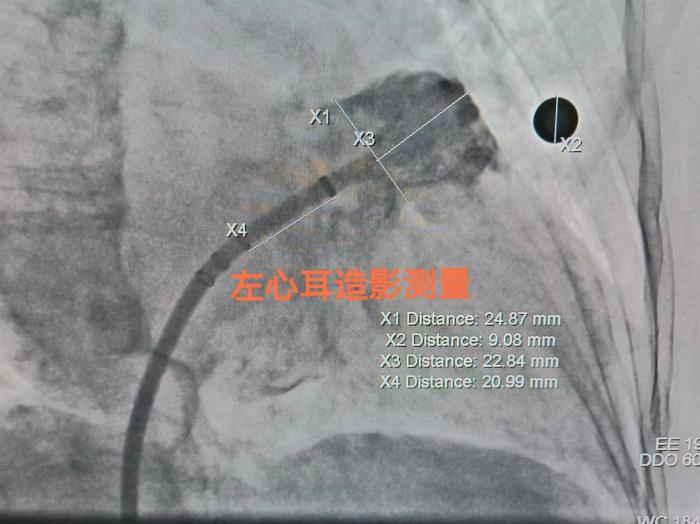

心血管内二科周玉庆副主任医师接诊曾奶奶后,根据房颤卒中及出血风险评分,判断该患者存在“高卒中、高出血”风险,经与患者和家属商定后,通过心血管内二科介入团队充分术前讨论、综合评估,决定对该患者实施房颤射频消融+极简式左心耳封堵“一站式”手术,控制心衰症状的同时还可以有效预防中风,为房颤治疗打上“双保险”。

周玉庆副主任介绍,房颤是老年常见的心律失常,心衰和卒中是房颤常见的两大危害,其中九成以上房颤血栓藏在心脏的“小耳朵”—左心耳里。房颤射频消融是使用导管,通过消融的方法将心律失常的病灶消除或隔离,从而终止房颤。而左心耳封堵是将封堵器植入到左心耳,从而防止血栓的形成。“通过一站式手术,患者可以在一次手术中同时完成射频消融和左心耳封堵两个治疗过程,避免了多次手术的风险和不便。”周玉庆说,“但对于手术操作而言,却是不小的挑战,再加上患者脊柱重度侧弯、血管径路迂曲、心脏转位等多重原因,手术难度比较大。”